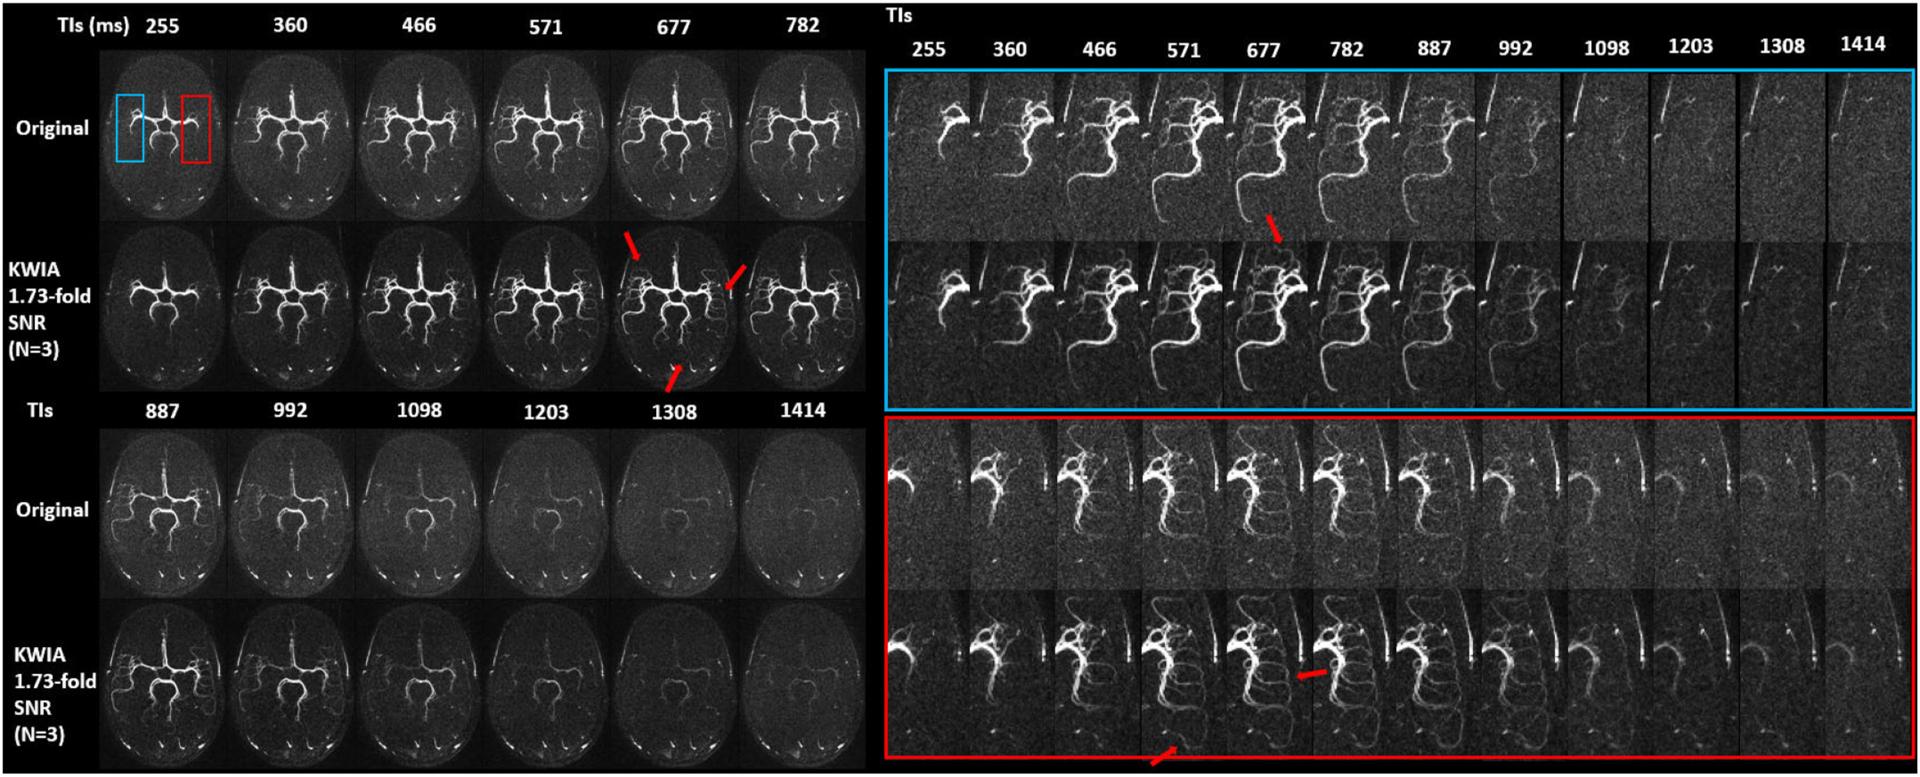

A novel denoising algorithm termed k-space weighted image average (KWIA) was proposed to improve the signal-to-noise ratio (SNR) of dynamic MRI, such as arterial spin labeling (ASL)-based dynamic magnetic resonance angiography (dMRA) and perfusion imaging. KWIA divides the k-space of each time frame into multiple rings, the central ring of the k-space remains intact to preserve the image contrast and temporal resolution, while outer rings are progressively averaged with neighboring time frames to increase SNR. Simulations and in-vivo dMRA and multi-delay ASL studies were performed to evaluate the performance of KWIA under various MRI acquisition conditions. SNR ratios and temporal signal errors between KWIA-processed and the original data were measured. Visualization of dynamic blood flow signals as well as quantitative parametric maps were evaluated for KWIA-processed images as compared to the original images. KWIA achieved a SNR ratio of 1.73 for dMRA and 2.0 for multi-delay ASL respectively, which were in accordance with the theoretical predictions. Improved visualization of dynamic blood flow signals was demonstrated using KWIA in distal small vessels in dMRA and small brain structures in multi-delay ASL. Approximately 5% temporal errors were observed in both KWIA-processed dMRA and ASL signals. Fine anatomical features were revealed in the quantitative parametric maps of dMRA, and the residuals of model fitting were reduced for multi-delay ASL. Compared to other conventional denoising methods, KWIA is a flexible denoising algorithm that improves the SNR of ASL-based dMRA and perfusion MRI by up to 2-fold without compromising spatial and temporal resolution or quantification accuracy.